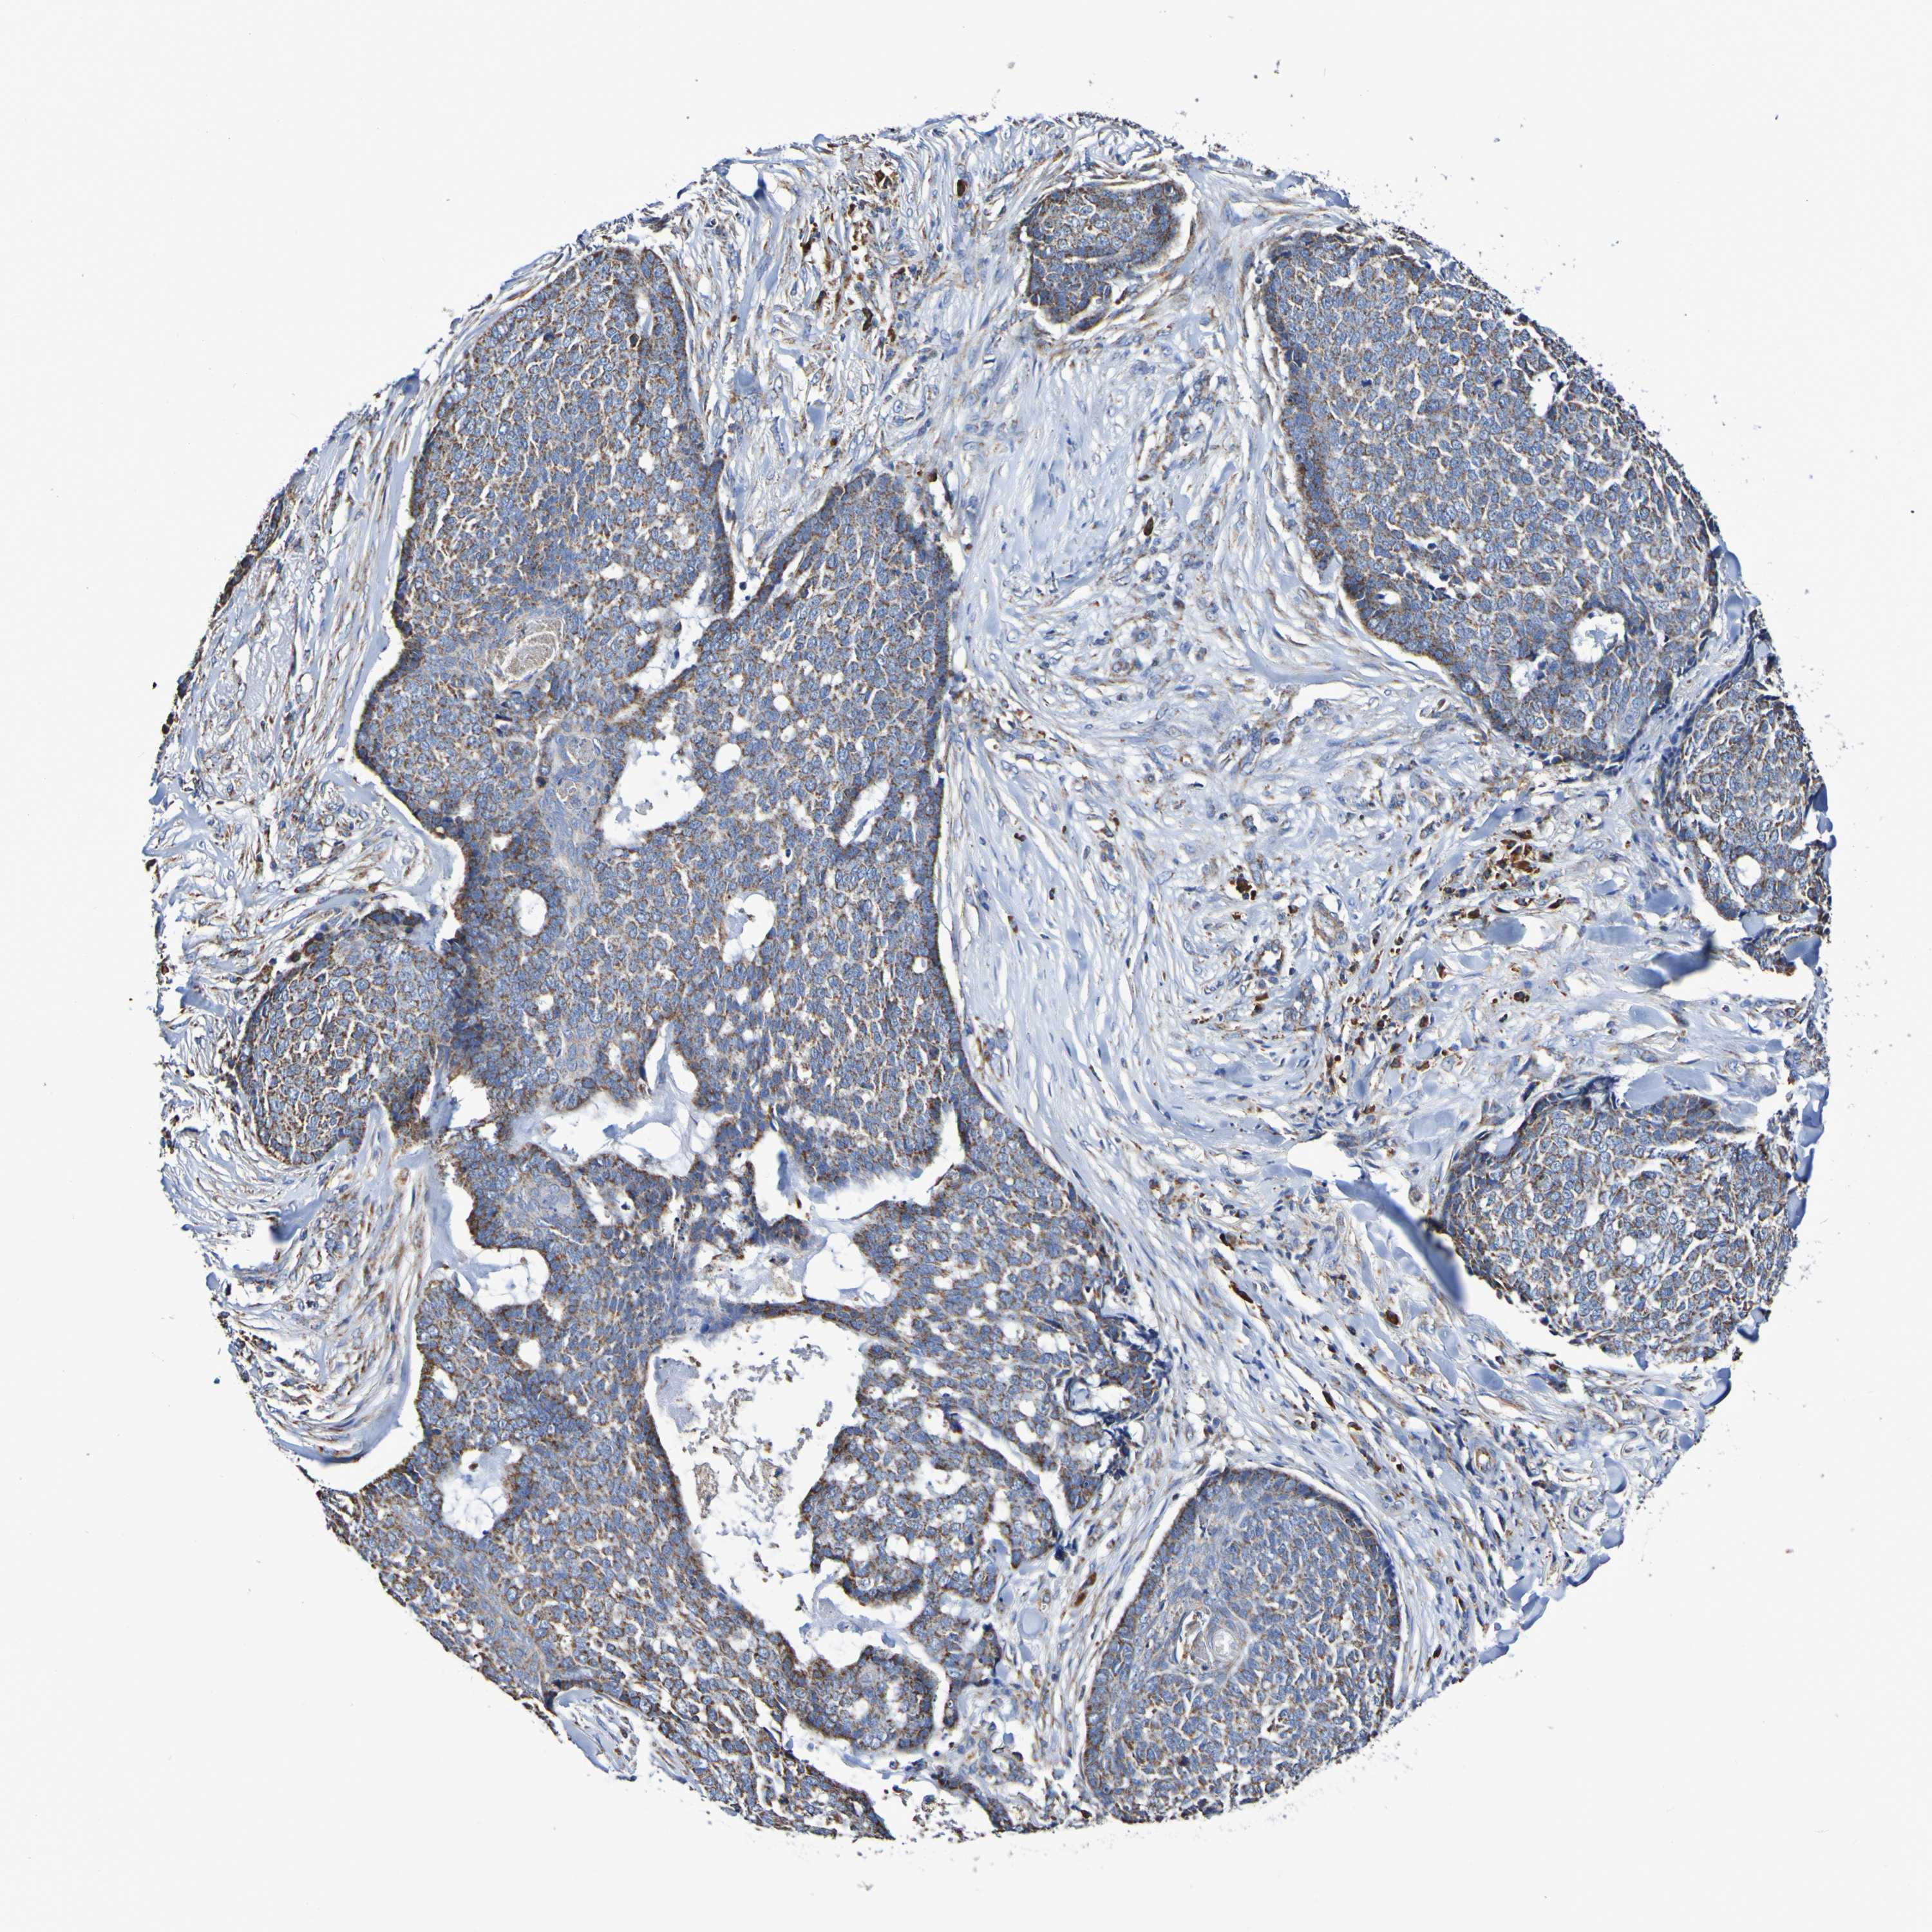

CANCER SKIN CANCER Show tissue menu

Basal cell and squamous cell cancer

SKIN CANCER - Protein expressioni

A mouse-over function shows sample information and annotation data. Click on an image to view it in a full screen mode. Samples can be filtered based on level of antibody staining by selecting one or several of the following categories: high, medium, low and not detected. The assay and annotation is described here.

Each image is clickable and will lead to virtual microscopy that enables deeper exploration of all samples and also displays staining intensity scores, fraction scores and subcellular localization as well as patient and tissue information for each sample.

Antibody HPA007615

Staining

High

Medium

Low

Not detected

Intensity

Strong

Moderate

Weak

Negative

Quantity

>75%

75%-25%

<25%

None

Location

Nuclear

Cytoplasmic/membranous

Cytoplasmic/membranous,nuclear

Squamous cell carcinoma, NOS

Basal cell carcinoma

Adnexal tumor, benign